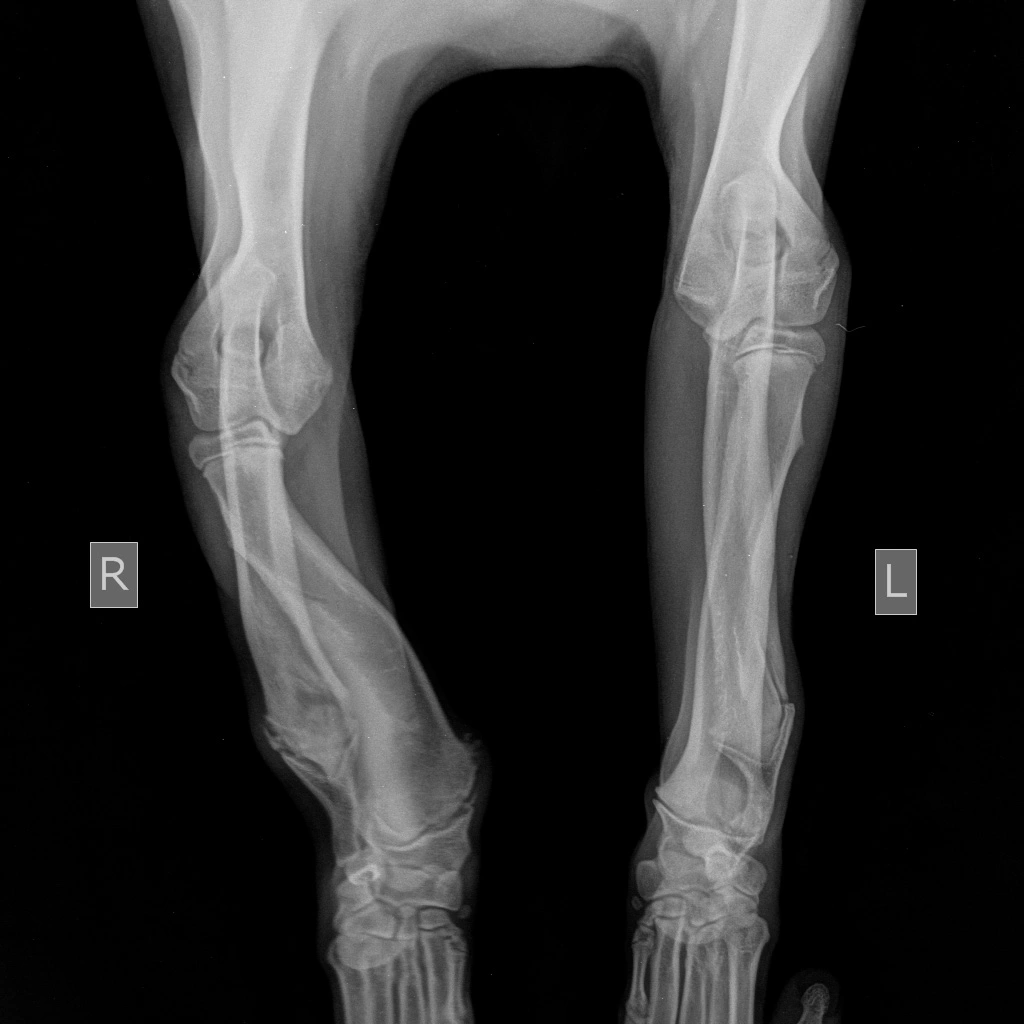

Предплечье состоит из двух костей (лучевой и локтевой), в норме они развиваются синхронно. При заболевании отмечается раннее закрытие зоны роста локтевой кости, что останавливает ее рост, в то время как лучевая кость продолжает увеличиваться в длину. Дальнейшему росту кости препятствуют локтевые и запястные суставы, что вызывает избыточное давление на них и искривление самой кости. Патологическое давление на сустав вызывает развитие дегенеративного изменения хряща (артроза, артрита, остеоартрита).

Основными клиническим признаками является нарастающая хромота и искривление лап в области запястья (так называемый «размет лап», а также припухлость в области локтевого сустава и его малоподвижность).

Диагноз ставится на основании анамнеза, ортопедического осмотра и инструментальных методов диагностики, таких как рентгенография и компьютерная томография (КТ), при которых врач может оценить стадию заболевания и выбрать подходящую тактику лечения.